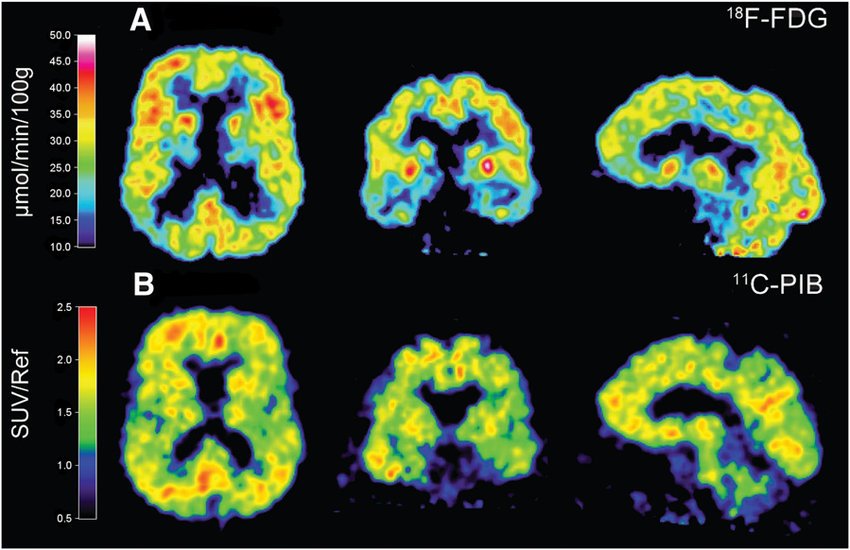

However, modern brain imaging has revealed another consistent feature: reduced metabolic activity in key memory regions years before symptoms appear.

Positron emission tomography (PET) scans show that the brain’s ability to use glucose — its primary fuel — declines early in the disease.

Brain PET scan comparison showing reduced glucose metabolism in Alzheimer’s patients